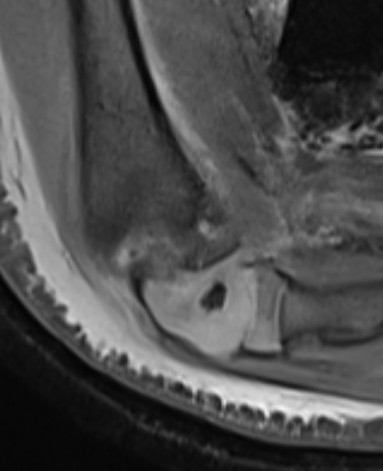

Ultrasound

MRI

Arthrogram

May need arthrogram to visualize distal humerus epiphysis

AVN post reduction and K wire in a 2 year old